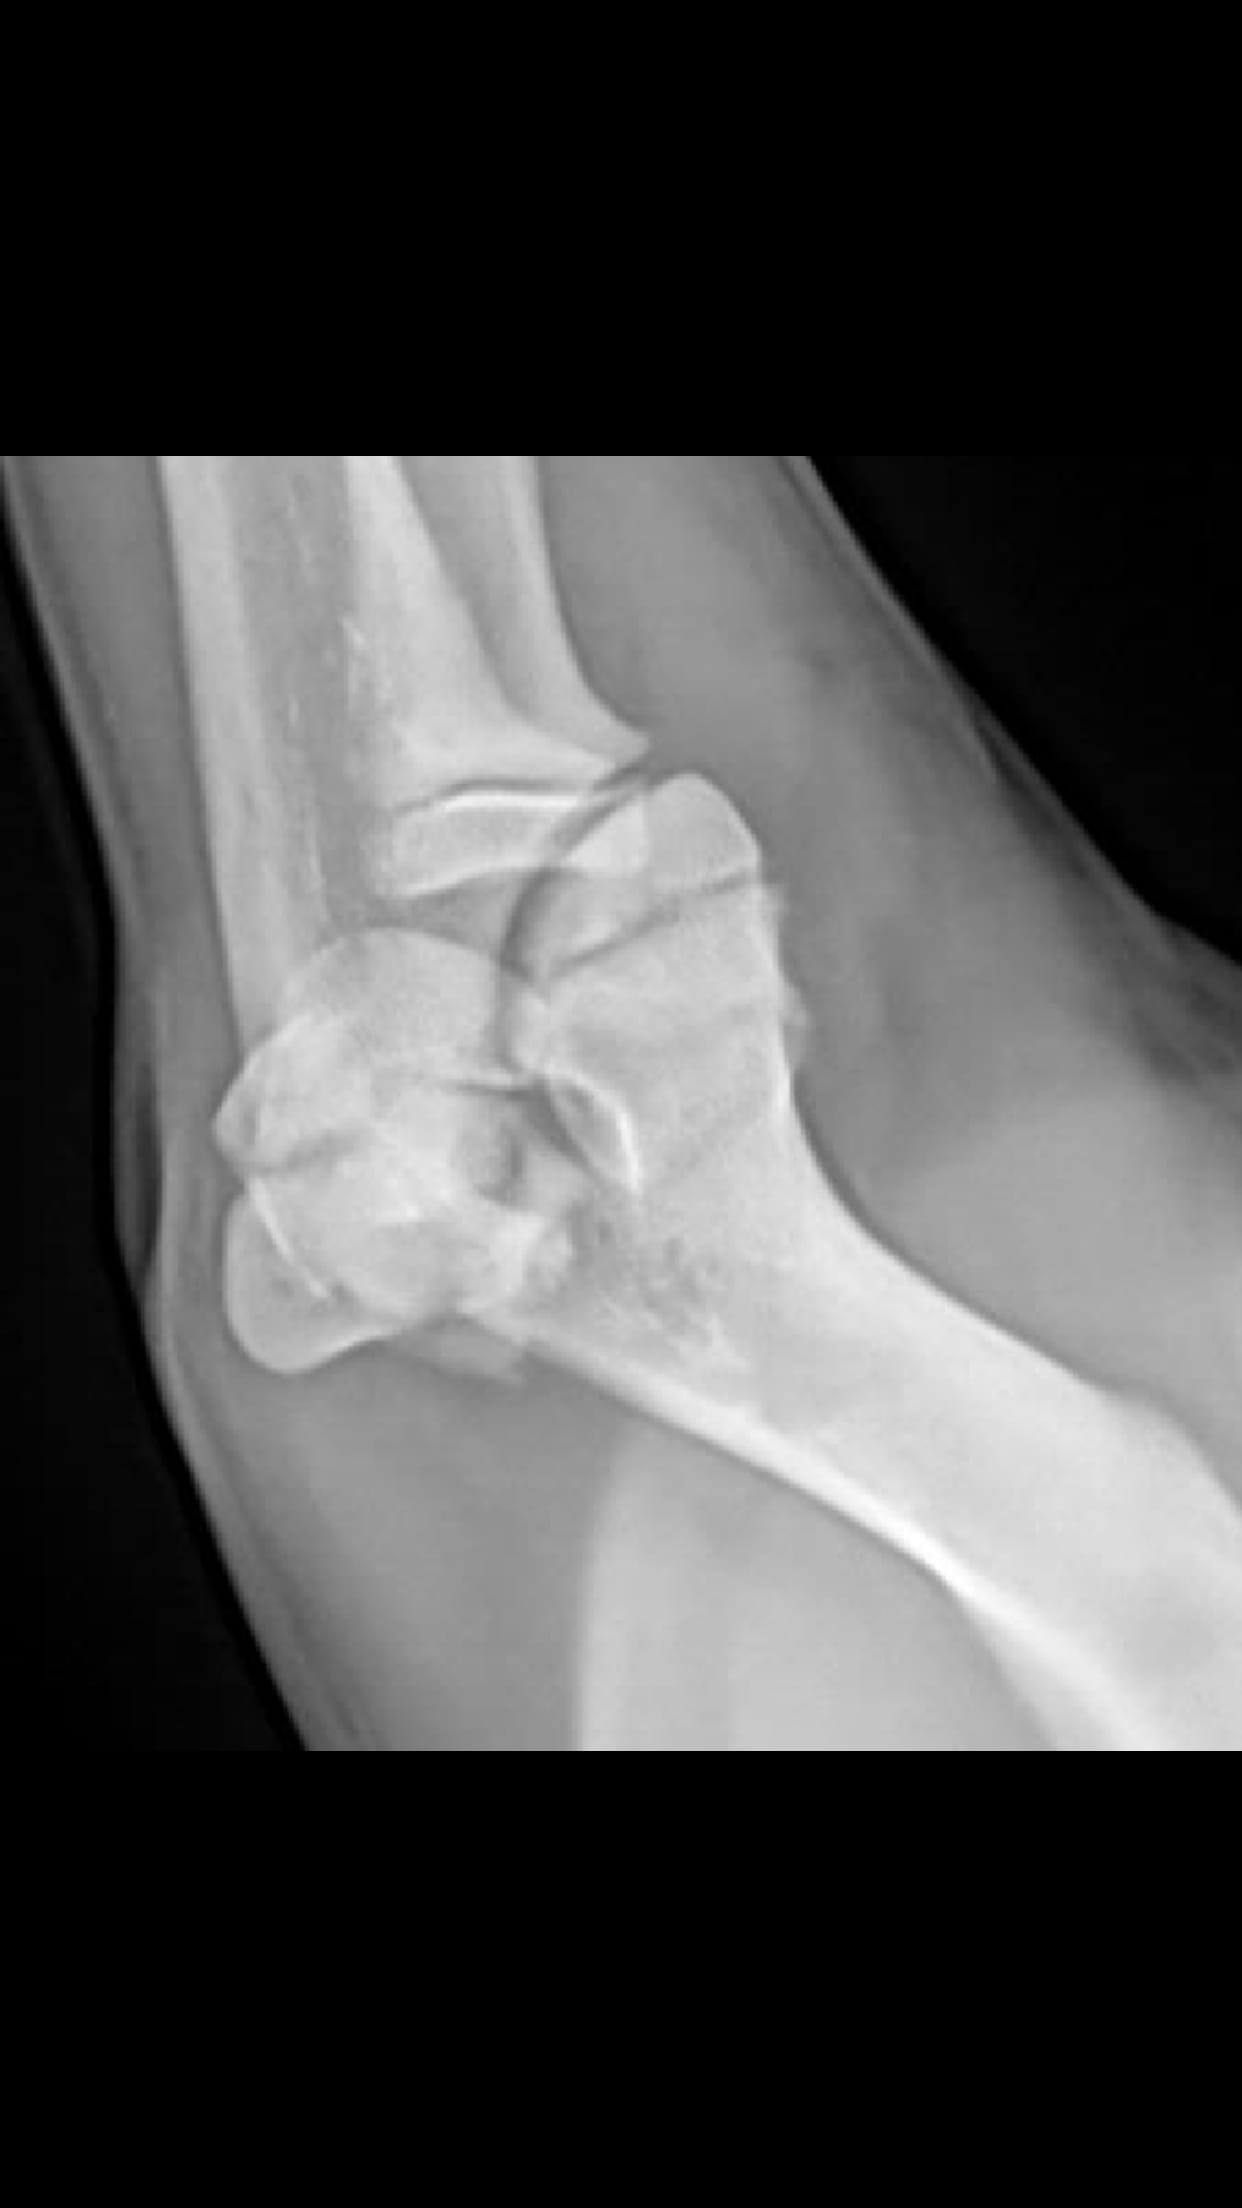

Is surgery necessary for my 4-month-old bulldog's fractured elbow?

My English bulldog jumped and landed wrong fracturing his elbow. My vet recommending surgery but wanted to confirm if surgery is route to go, or a splint will be ok? My puppy’s is 4 months old

Hi, it is impossible to keep an elbow still enough to allow healing of the fracture.. being a joint there is always the tendency to move. So yes I agree that surgery would be the way forward. Hope Rubble makes a speedy recovery.!

I am so sorry Bleu fell and fractured his elbow! Without seeing him in person or the x-rays, I can't say for certain a splint is a viable option. I will, however, give you my opinion on the situation with what you have told me. I would do the surgery. Bleu is a young puppy who still has growing to do, and conservative treatment (splint and rest) runs the risk of affecting the growth of his leg should it not heal correctly. An incorrectly healed fracture could be painful, and would impact on his movement. That would mean surgery down the line to fix this abnormal growth and incorrectly healed fracture. It's best to have the surgery done to ensure the fractured bones heal in their correct anatomical position, and so there isn't an impact on his growth or movement. You are certainly welcome to take Bleu into another vet for a second opinion, but my opinion based on my experience is to have the surgery done.